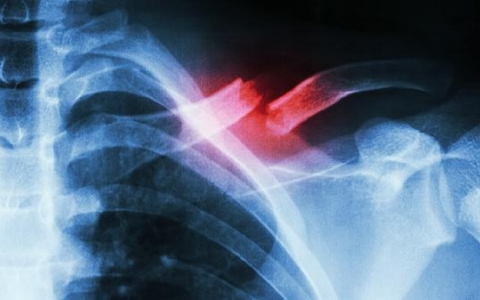

肋软骨炎会不会引起后背中间疼

肋软骨炎可能引起后背中间疼痛,治疗可通过药物、物理疗法和生活方式调整缓解症状。肋软骨炎是肋骨与胸骨连接处的软骨发生炎症,炎症刺激可能放射至后背中间区域,导致疼痛